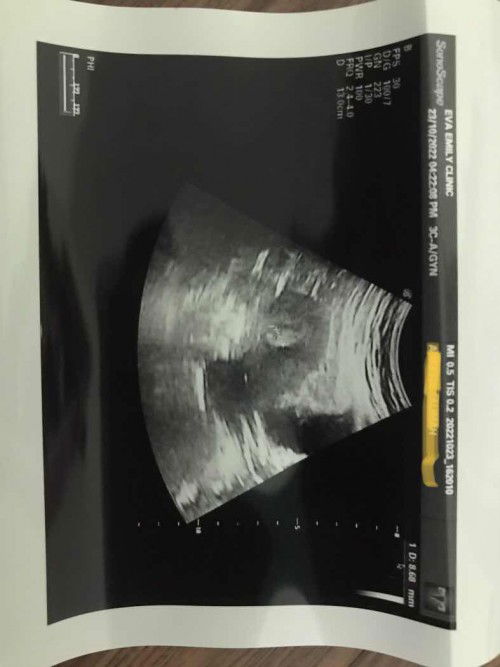

Hai semua. saya baru scan baru ni.pic ni dktr cuma cakap dnding rahim tengah menebal.jadi ada kemungkinan nak pregnant tau nak period.due klu ikut bln lpas lg bbrpa hari. Cek upt bbrpa hari lepas masih samar.kalau tgkp pic mmg xnmpk sgt. adakah dekat tengah rahim tu janin yg baru nak membentuk?#ingintahu